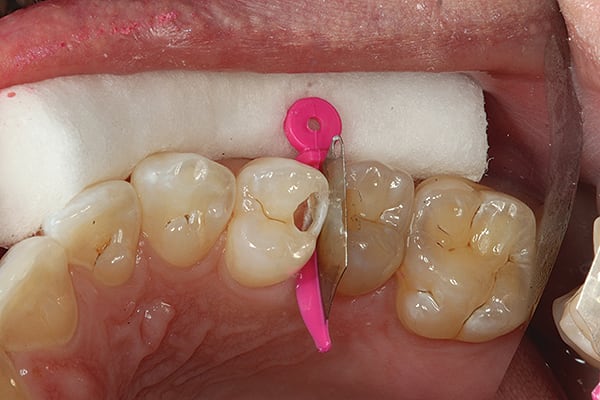

1. Initial incipient Class II decay. The first tunnel has been completed. Note the decalcification left on the proximal wall but the decay removed and the wall perforated through up to the matrix band (Triodent WedgeGuard, Ultradent, www.ultradent.com).